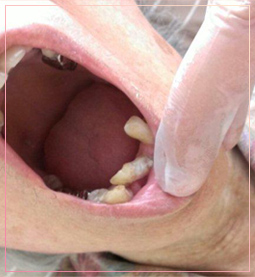

高齢の方ですが歯周病が進行していくとグラグラしてしまい抜け落ちてしまいます。

横に倒れたような感じになってます。

その周りに白く写っているのが歯垢と呼ばれる汚れです。